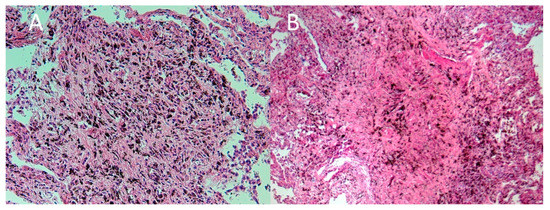

2. Case Report

3. Autopsy